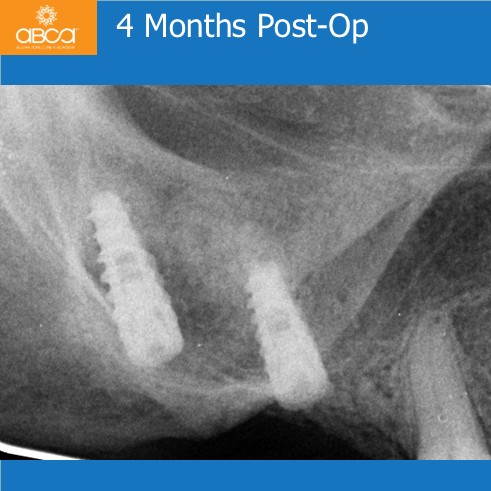

Categories3-6 Months, Augma Bone Cement Academy, Augma Lift™, Bond Apatite®, Bone Cement Expert, Clinical Cases, Closed Sinus Lift, Images, Kit A, Post-Op Period, Sinus Lift, Upper Right Molar March 2, 2026 Sinus Lift with Augma Lift™ Kit A – Missing Tooth #16 (3) Less than 2 mm of sub-sinus bone height Post navigationPrev Rehabilitation of the Left Maxilla, with Immediate Implant Placement Next Augma Simplified Webinar Leave a Reply Cancel replyYou must be logged in to post a comment.